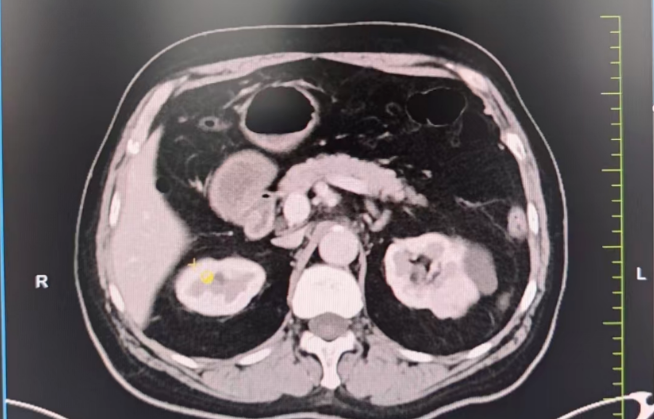

生死抉擇:心臟術(shù)后又遇腎腫瘤,求醫(yī)之路一波三折。3年前,劉大爺因嚴(yán)重冠心病接受了心臟搭橋手術(shù),并置換主動(dòng)脈瓣生物瓣。術(shù)后長(zhǎng)期服用阿司匹林抗凝,病情相對(duì)穩(wěn)定。然而半年前,一次體檢發(fā)現(xiàn)他的左腎長(zhǎng)出一枚直徑3×2cm的腫瘤,需盡快手術(shù)切除。

難題接踵而至 1.保腎難題:劉大爺保腎臟意愿強(qiáng)烈,需行高難度的腹腔鏡腎部分切除術(shù),但因劉大爺心臟術(shù)后長(zhǎng)期口服阿司匹林抗凝,對(duì)于保腎手術(shù)增加了出血風(fēng)險(xiǎn)高。2.心臟高風(fēng)險(xiǎn):多家醫(yī)院評(píng)估后認(rèn)為,劉大爺心臟功能較差(心功能Ⅱ級(jí)),術(shù)中可能出現(xiàn)心衰、血栓等致命風(fēng)險(xiǎn),拒絕手術(shù)。

兩大難關(guān),精準(zhǔn)突破1. 心臟“護(hù)航”計(jì)劃:由醫(yī)院副院長(zhǎng)、心血管中心主任隋立有牽頭,調(diào)整抗凝方案:術(shù)前7天停用阿司匹林,改用低分子肝素橋接,降低術(shù)中出血風(fēng)險(xiǎn)。優(yōu)化心臟功能:控制血壓,確保心功能穩(wěn)定在Ⅱ級(jí)。術(shù)中全程心電監(jiān)護(hù),實(shí)時(shí)調(diào)控血壓、心率,預(yù)防心肌缺血。 2. 保腎“微創(chuàng)”方案:泌尿外科團(tuán)隊(duì)在張寶主任的帶領(lǐng)下決定采用后腹腔鏡下腎部分切除術(shù),最大限度保留正常腎組織,術(shù)中控制出血量<50ml,手術(shù)時(shí)間縮短至1.5小時(shí),大幅降低心臟負(fù)荷,術(shù)后轉(zhuǎn)入重癥監(jiān)護(hù)室(ICU)密切監(jiān)測(cè),24小時(shí)專人監(jiān)護(hù)心肺功能。